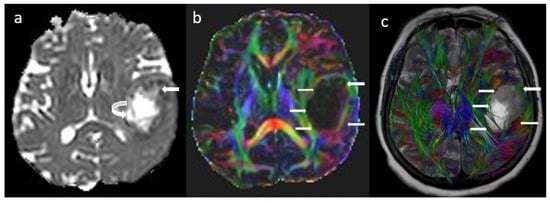

The Role of Advanced MR Imaging in Gliomas

by Anastasia K. Zikou, Eleni Romeo, George A. Alexiou, Marios Lampros, Spyridon Voulgaris, Loukas Astrakas and Maria I. Argyropoulou

Gliomas are a significant health problem with a lot of imaging challenges. The role of imaging is no longer limited to only providing anatomic details, but with the advancement of Magnetic Resonance Imaging (MRI) techniques, it now permits the assessment of the freedom [...] Read more.

Gliomas are a significant health problem with a lot of imaging challenges. The role of imaging is no longer limited to only providing anatomic details, but with the advancement of Magnetic Resonance Imaging (MRI) techniques, it now permits the assessment of the freedom of water molecule movement, the microvascular structure, the hemodynamic characteristics, and the chemical makeup of certain metabolites of lesions. These advanced imaging techniques include diffusion-weighted imaging, diffusion tensor imaging, dynamic contrast-enhanced MRI, Magnetic Resonance (MR) perfusion, MR angiography, and magnetic resonance spectroscopy. their role in the diagnosis, classification, and post-treatment follow-up of gliomas, as well as their application in radiogenomics and glioma analysis with the aid of artificial intelligence, is presented and discussed. Full article

Show Figures

Figure 1